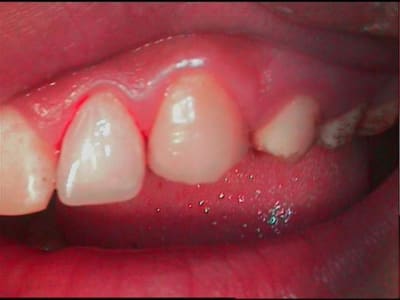

tiens! pendant que je suis en pedo, et que mac est occupé ailleurs, la suite, donc en definitive, glumla et flow,pas de taille,pas d'etching,pas de sensibilité post op, je crains pour les faces occl des post, sinon ça filoche pas trop mal pour l'instant...

2 lb5hv9 - Eugenol

2bis gwdkbq - Eugenol